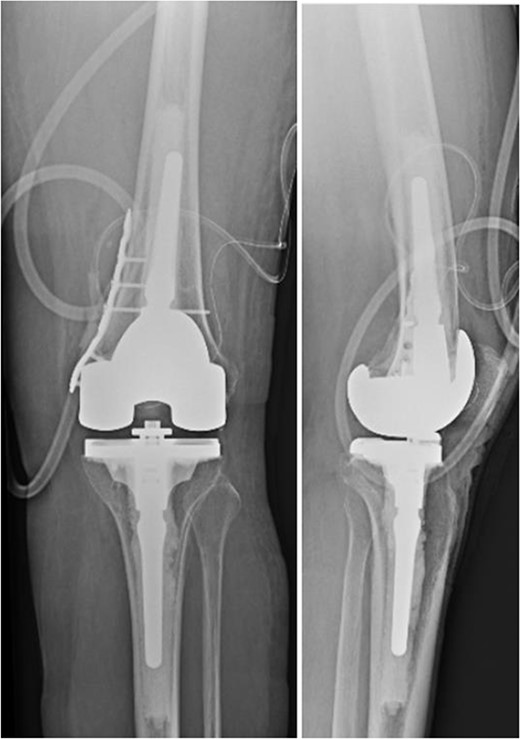

We present the case of a 76 year old Hispanic female previously managed for tri-compartmental osteoarthritis and lateral condyle insufficiency fracture of the left knee. She was being managed conservatively; however, the pain began to affect her well-being and activities of daily living (ADL). Most recently the patient suffered a mechanical ground level fall resulting in an ipsi-lateral medial condyle fracture as seen in Fig. 1. Single staged left knee medial condyle ORIF and CCK arthroplasty through a medial para-patellar approach was performed. The medial condyle fracture was reduced and stabilized using a 5-hole distal fibula locking plate in buttress mode. After fracture stabilization, a CCK arthroplasty was performed. Immediate post-operative imaging is seen in Fig. 2. Intra-operative photos are demonstrated in Fig. 3. The patient was made non-weight bearing for 2 weeks followed by weight bearing as tolerated (WBAT). An early weight bearing protocol was used given the majority of forces during ambulation would be placed through the total knee implant and not place significant stress on the medial condyle ORIF. At 3 months post-operatively, the patient obtained 0–120° range of motion (ROM) and was freely WBAT. At 8 weeks, however, the patient required a manipulation under anesthesia for regressing to 0–95° ROM. Figure 4 demonstrates intra-operative images of the manipulation. At 3 years follow up, her ROM was 5–95 with good strength without any further complication or subsequent procedures. Three years post-operatively the patient reported improved function with ADLs, significantly improved pain, and better mental health.

Two post-operative radiographs of the left knee demonstrating the constrained condylar knee arthroplasty, along with the open reduction internal fixation of the medial condyle using a distal fibula locking plate in buttress mode.